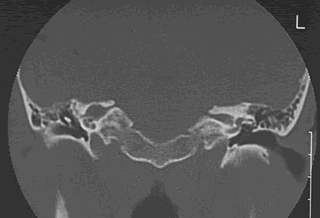

Tomografia computada: Notamos el desgaste del Conducto auditivo interno

Fig5 : Corte Axial-Frontal